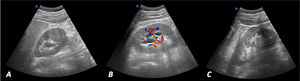

Ante el cuadro sugestivo de cólico renoureteral derecho, se decide realizar ecografía a pie de cama en consulta con los siguientes hallazgos: riñón derecho con dilatación de la vía excretora sugerente de hidronefrosis grado II/IV (figs. 1A y B). Vejiga bien replecionada con imagen anecoica tubular en el corte longitudinal que corresponde al uréter distal dilatado (fig. 2A). En el interior de la vejiga se observa imagen anecoica con borde hiperecoico bien definido que sugiere ureterocele y en su interior, una imagen hiperecoica con sombra acústica posterior de 9,76mm compatible con litiasis (fig. 2B). Riñón izquierdo (fig. 1C), hígado, vesícula y vía biliar intra y extrahepática, bazo, zona pancreática y próstata sin alteraciones.

La prueba diagnóstica de elección es la ecografía, donde podrá detectarse una imagen en la pared posterior de la vejiga delimitada por una línea hiperecogénica bien definida, redondeada, de pared fina, que cambia de tamaño durante la exploración en tiempo real, sin doppler en su interior. En ocasiones se puede visualizar el uréter dilatado en la zona posterior a la vejiga2,5, como el descrito en este caso. Los uréteres son estructuras de calibre muy estrecho no visibles en ecografía de forma habitual6, salvo en situaciones patológicas donde sufran gran dilatación, como se muestra en la figura 2A. La ecografía permite, además, valorar complicaciones derivadas del ureterocele, como la dilatación del tracto urinario (reflejo ureterovesical o hidronefrosis), permitiendo establecer el grado y gravedad de la afectación renal2,5. El estudio se puede completar con otras técnicas como cistografía, urografía intravenosa, gammagrafía renal, cistoscopia y tomografía axial computarizada (TAC), según cada caso4,5.